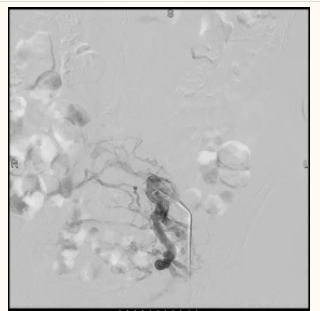

3月21日,经过充分的术前准备,张卫平、副主任医师王军为患者实施了局麻下的“临时下腔静脉滤器置入术”减少开通过程中血栓脱落导致肺栓塞发生风险,随后又进行了“左髂静脉开通及球囊扩张术”、“髂静脉支架置入术”,术后复查造影见支架位置良好,支架将部分血栓压至管壁,再发血栓脱落导致肺栓塞风险较小,又取出拦截血栓的临时滤器,仅用了1个小时就顺利完成了手术,腹股沟区针眼只有米粒那么大,第二天患者左下肢肿胀就完全消失了,也可以正常活动。

06.png

临时滤器的保护下开通髂静脉并逐级扩张扩张后仍严重狭窄